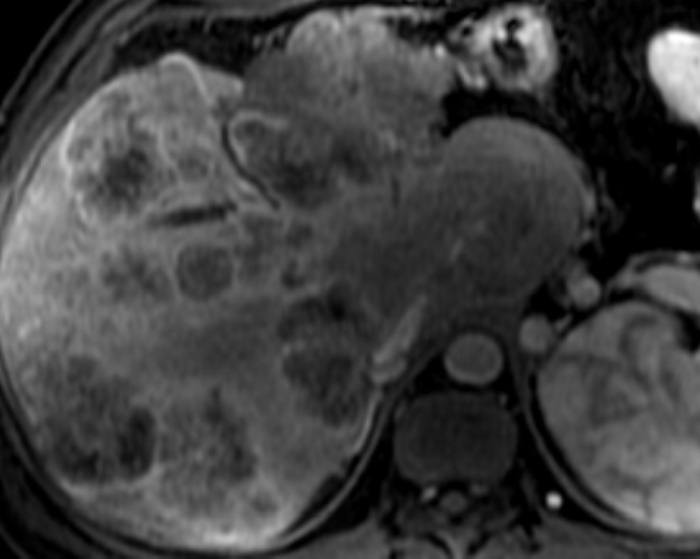

Di căn gan

» Thông tin: Nam giới – 37 tuổi.

» Lâm sàng: Tiền sử K đại tràng.